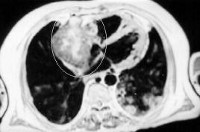

Данные ЭКГ при опухолях сердца полиморфны и малоспецифичны: они могут отражать признаки гипертрофии камер сердца, нарушения проводимости и ритма, ишемию миокарда и т. д. Рентгенография органов грудной клетки чаще всего выявляет увеличение размеров сердца и признаки легочной гипертензии. Более чувствительным методом диагностики опухолей является УЗИ сердца: с помощью чреспищеводной ЭхоКГ лучше визуализируются опухоли предсердий, путем трансторакальной ЭхоКГ – опухоли желудочков.

При сомнительных результатах диагностики выполняется МРТ и МСКТ сердца, радиоизотопное сканирование, зондирование полостей сердца и вентрикулография. Для верификации гистологической структуры опухоли сердца проводится ее биопсия в процессе катетеризации или диагностической торакотомии. При экссудативном перикардите ценную диагностическую информацию может дать цитологическое исследование жидкости, полученной при пункции перикарда. Дифференциальная диагностика опухолей сердца проводится с ВПС, миокардитом, кардиомиопатиями, перикардитом, амилоидозом сердца.